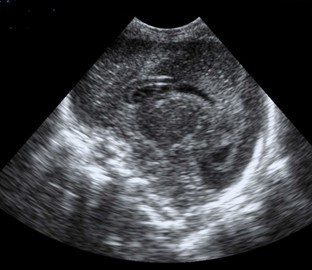

Neonatology Prolongation of Ventricles Image